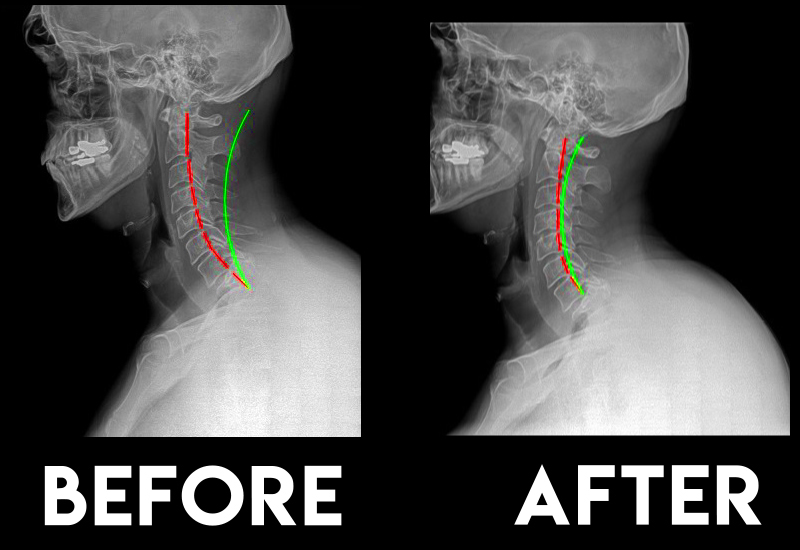

We Get Results: